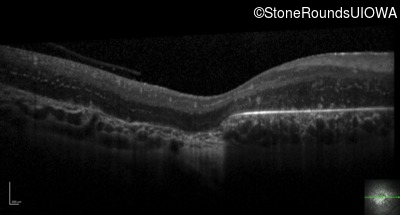

Optical Coherence Tomography - Right - 20/80 -1

Exemplar / OCT Stack

OCT Stack

Optical Coherence Tomography - Left - 20/100 -2